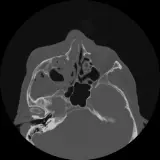

Congenital Hearing Loss

A review of congenital hearing loss, including an approach to cochlear abnormalities

13 cases